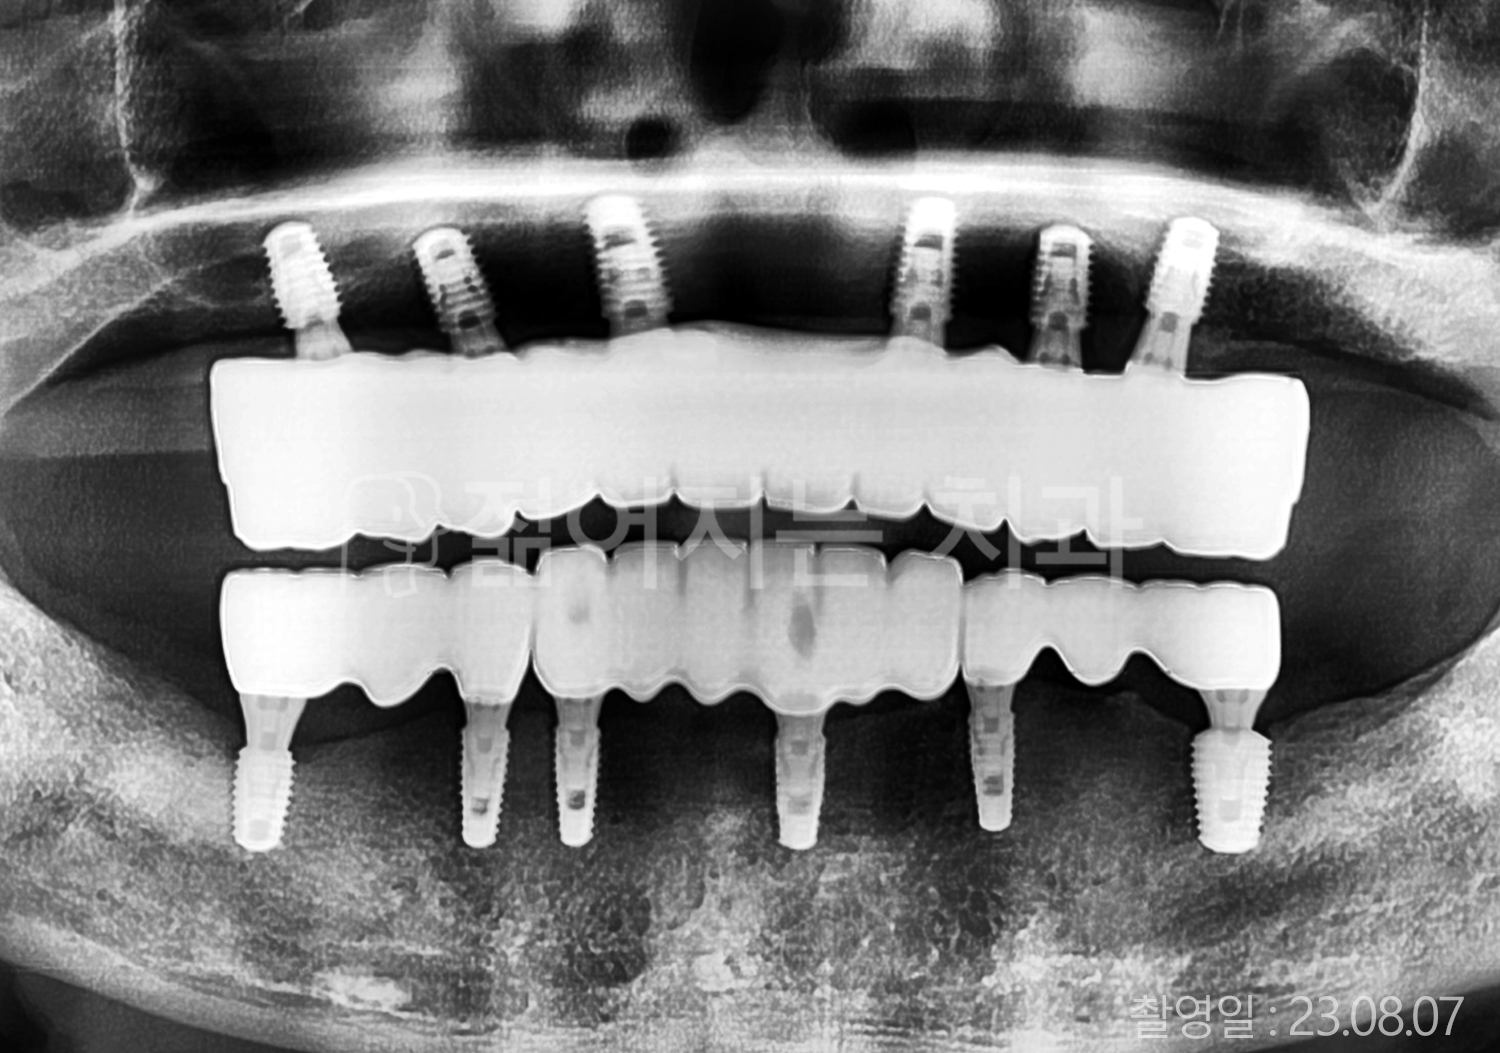

• 40대 전체치아 10개 이상 임플란트

• 50대 전체치아 10개 이상 임플란트

• 50대 고혈압, 당뇨, 고지혈증 전체치아 10개 이상 임플란트